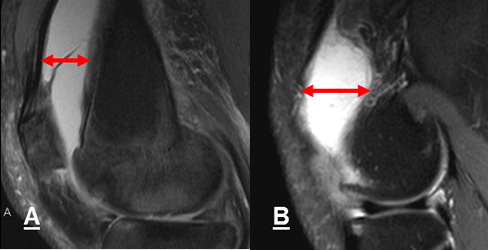

Fig 52 A. Fractura de patela.

A: Rx AP. Sutil imagen radiolúcida, en el borde superointerno de la patela.

B: TAC axial y C: TAC reconstrucción coronal. Se confirma fractura vertical y no desplazada de la patela.